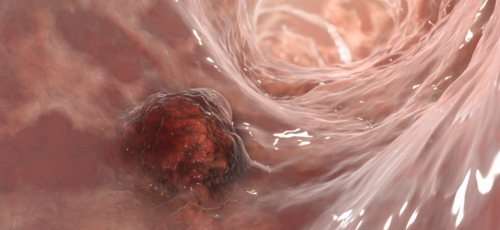

대장이라는 기관은 우리 몸 소화기관의 마지막에 있는 부위인데요 길이는 1.5m가량 되며, 소장 다음으로 길이가 긴 장기로 대변이 만들어지는 최종 마지막 장기입니다. 암이 결장에 생기면 결장암, 직장에 생기면 직장암이라고 하는데요 이를 통상적으로 대장암이라고 합니다. 즉 대장암이란 결장이나 직장에 생기는 악성 종양으로 대부분이 점막의 샘 세포에 생기는 경우입니다.

보통 발병률이 높은 암으로 위암을 많이 이야기하지만 최근 10년 사이 대장암 환자가 2배 정도 증가하여 위암과 비슷한 수준의 발병률이 나타나고 있다고 합니다. 특히 초기에 자각하기 어려운 대장암은 국내에서 치사율이 3위를 차지할 정도로 위험한 질병에 속하는데요. 초기에는 대부분 아무런 증상이 나타나지 않기 때문에 대장암 초기증상이 조금씩 나타난다면 이미 많이 진행된 경우가 많다고 합니다. 그래서 그나마 초기에 눈에 띄는 대장암 초기증상들 몇 가지를 정리해보았습니다.